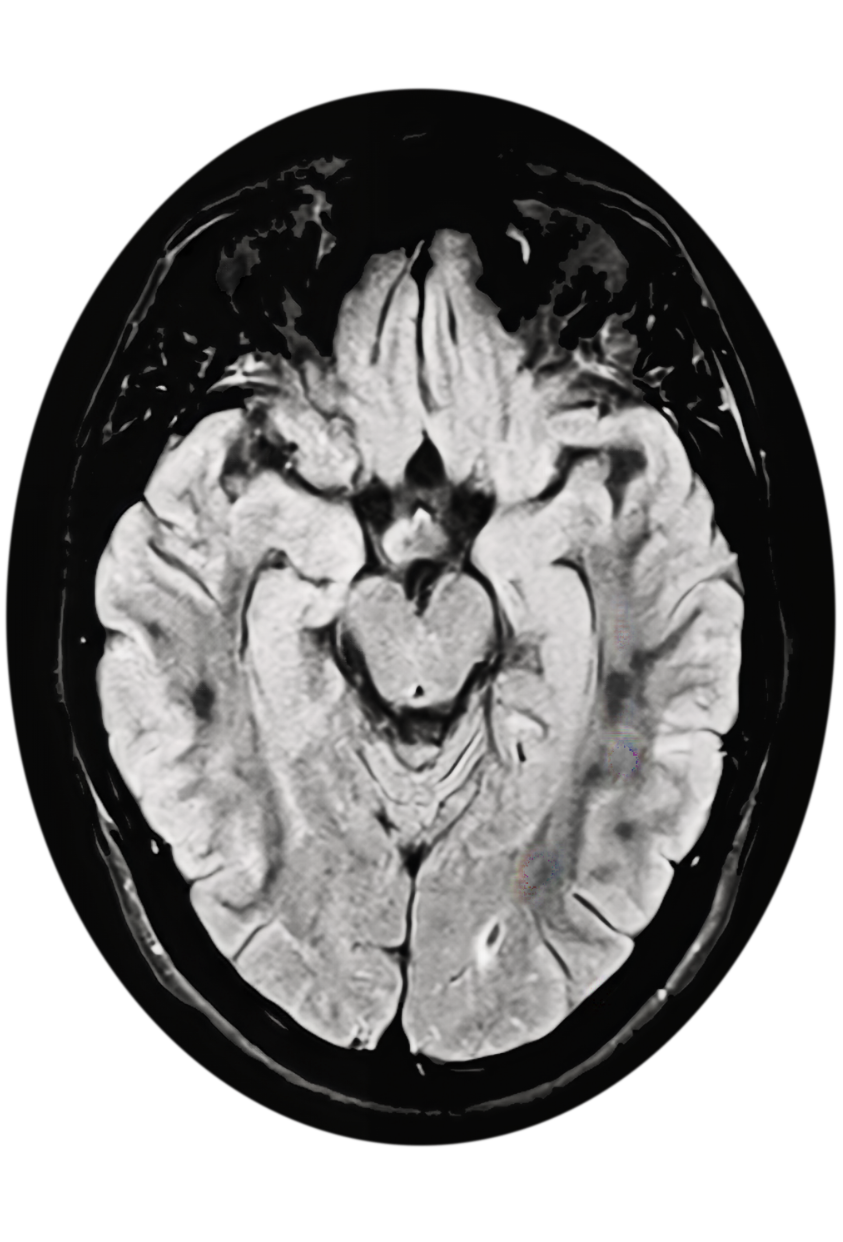

An MRI image of a brain in black and white.

MRI features

When a leukodystrophy or Alexander disease is suspected, prompt referral to a neurologist for a brain MRI and genetic testing is critical for timely diagnosis.11-14 Neuroimaging findings of frontally predominant white matter abnormalities, consistent with a leukodystrophy, are often observed in those with earlier age of onset.1,15 In those with a later age of onset, neurodegenerative features with brainstem lesions and/or atrophy of the brainstem, cerebellum, and/or cervical spinal cord are typically observed.4,14,16